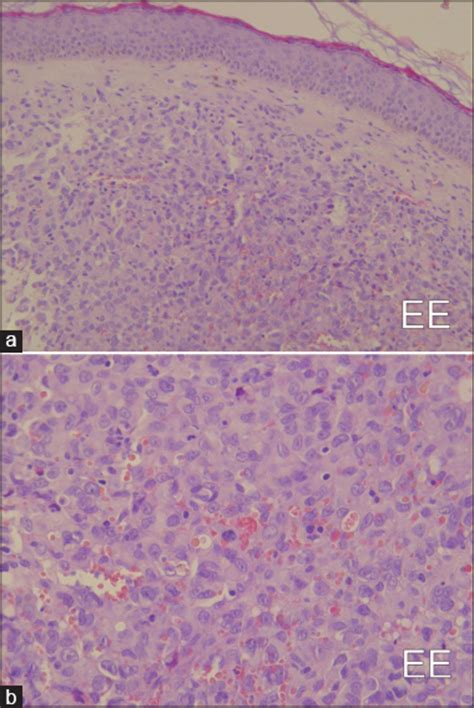

Merkel cell carcinoma (mcc) is a rare, aggressive form of skin cancer with a high risk for returning (recurring) and spreading (metastasizing) normal merkel cells in the skin: Merkel cells are connected to the nerve endings in the skin that are responsible for the sense of touch. They are nerve endings and provide information on mechanical pressure, position, and deep static touch features, such as shapes and edges. Merkel cells (mcs), the neuroendocrine cells of the skin, were believed to be at the origin of mcc due to their phenotypic similarities. Merkel nerve endings are mechanoreceptors, a type of sensory receptor, that are found in the basal epidermis and hair follicles. The tumour is centered in the dermis with frequent involvement of the overlying actinic keratosis and in situ squamous cell carcinoma is commonly found in the overlying skin (figure 2). The skin without hair is known as the glabrous skin; That's because gu and his research colleagues have proved that merkel cells— which contact many sensory nerve endings in the skin—are the initial sites for sensing touch.

After receiving a cancer diagnosis, your doctor will run tests to find out if the cancer has spread to other parts of your body. Merkel nerve endings are mechanoreceptors, a type of sensory receptor, that are found in the basal epidermis and hair follicles. Merkel cell carcinoma is a neuroendocrine carcinoma composed of densely blue cells. Merkel cells are found mainly at the base of the top layer of the skin (the epidermis). Merkel cells, found in the top layer of the skin, are very close to the nerve endings that receive the sensation of touch. Langerhans cells are dendritic but unpigmented and are found nearer the skin surface than melanocytes. They aid in the ability to sense light touch. They are associated with the sense of light touch discrimination of shapes and textures.

The tumour is centered in the dermis with frequent involvement of the overlying actinic keratosis and in situ squamous cell carcinoma is commonly found in the overlying skin (figure 2).

The skin over them is usually firm (not broken) and they don't hurt. Merkel cell carcinoma is highly treatable with surgical and nonsurgical therapies, particularly if caught early. In humans, merkel cells (yellow dot) are found clustered beneath the epidermal ridges (aka fingerprints). Merkel cells, found in the top layer of the skin, are very close to the nerve endings that receive the sensation of touch. However, for several reasons, for example, heterogeneous differentiation of mccs and postmitotic character of mcs, it is not very likely that mcc develops from differentiated. That's because gu and his research colleagues have proved that merkel cells— which contact many sensory nerve endings in the skin—are the initial sites for sensing touch. …contains two other cell types: The tumour is centered in the dermis with frequent involvement of the overlying actinic keratosis and in situ squamous cell carcinoma is commonly found in the overlying skin (figure 2).